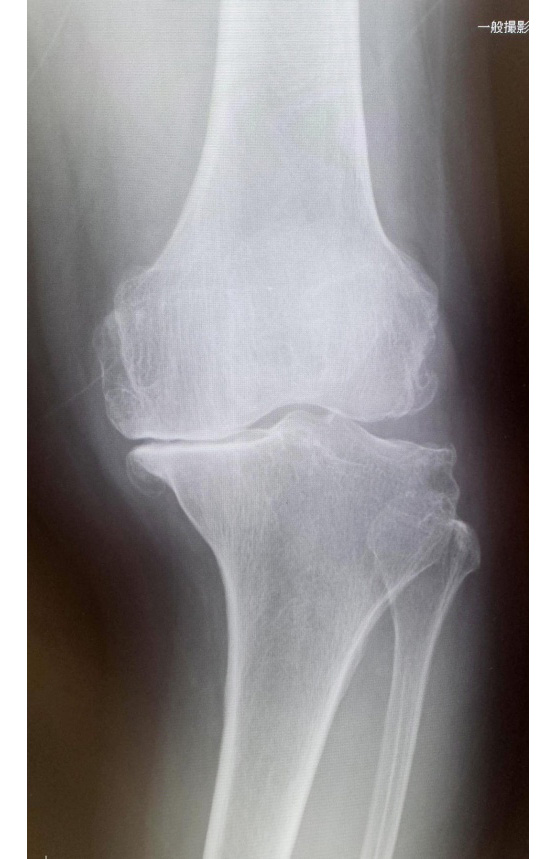

当院でおこなった人工膝関節全置換術(TKA)

手術前